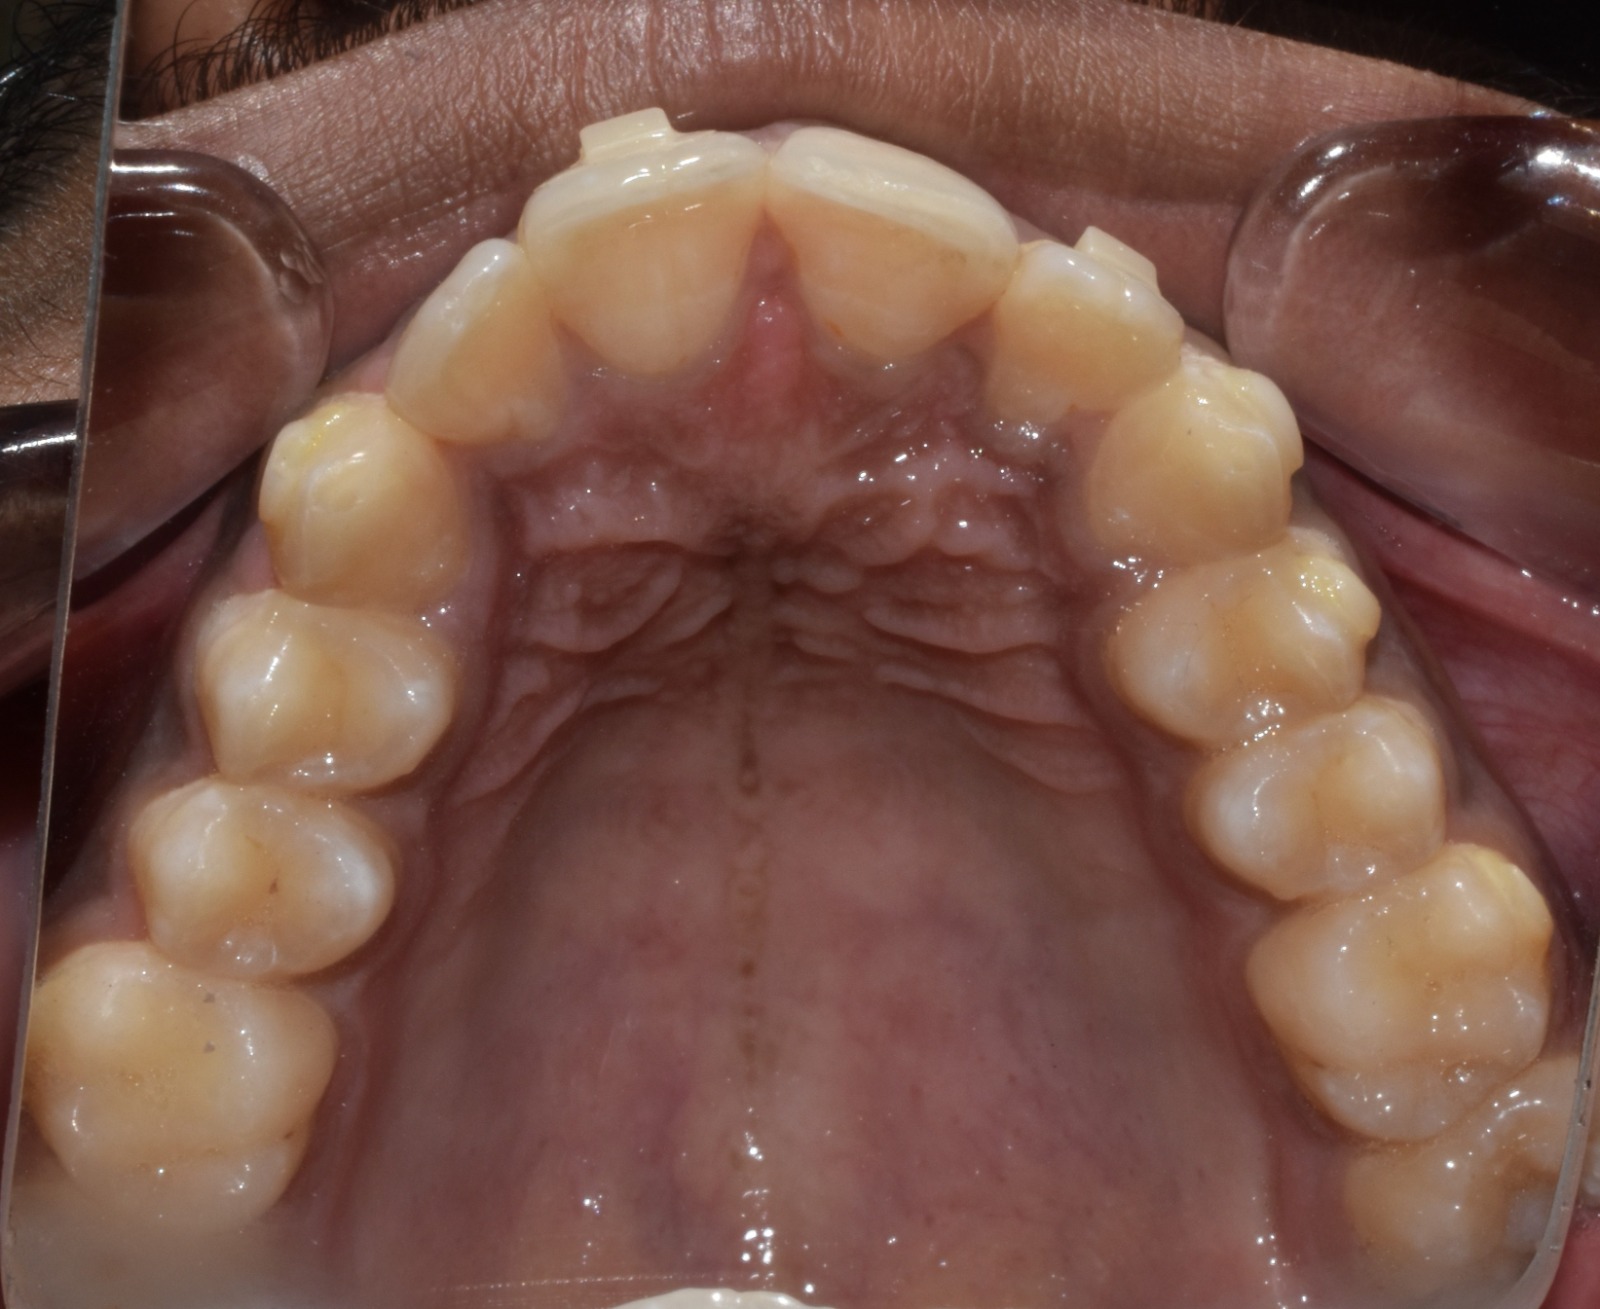

Before & After Results

At Aline Dent, we take pride in delivering visible and lasting improvements in our patients’ smiles. Our before-and-after results highlight the effectiveness of modern dental treatments combined with personalized care. This gallery showcases real dental cases treated at our clinic, giving you a clear idea of how different dental concerns can be corrected with the right treatment approach.

From minor corrections to complete smile enhancements, these teeth transformation results demonstrate how professional dental care can improve both oral health and appearance. Our experienced dental team carefully evaluates each patient’s needs and creates customized treatment plans to achieve natural, healthy, and confident smiles.

In this gallery, you will find a variety of smile makeover cases, including treatments for crooked teeth, gaps, discoloration, damaged teeth, and other common dental concerns.